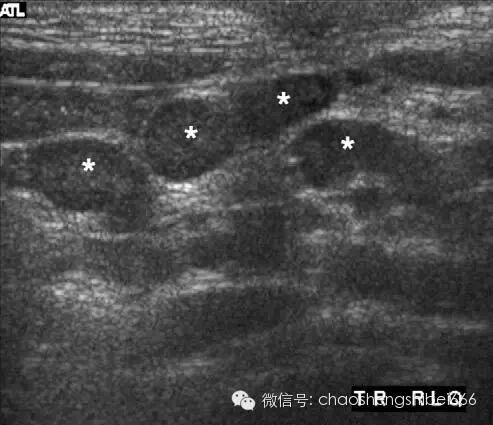

肠系膜淋巴结炎

诊断肠系膜淋巴结仍然存在争议,目前还没有被广泛接受。小儿在没有右下腹其它病变而发现淋巴结增大的情况下可能诊断肠系膜淋巴结炎(图5)。轻度增大的右下腹肠系膜淋巴结在儿童多为正常发现,且淋巴结肿大的标准目前还未被完全明确。肿大的淋巴结可能出现于不同的病理情况,如阑尾炎,感染性肠病,回肠炎,过敏紫癜性肠病。在笔者的医院不做肠系膜淋巴结炎的诊断。

5 3岁男孩的右下腹多发轻度肿大淋巴结(星号所示)。